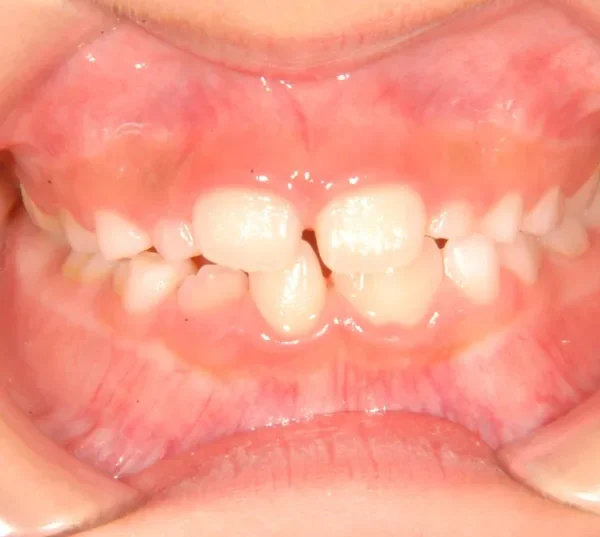

初診時年齢 小学校2年生 (男性) 主訴 癒合歯・永久歯が生えるスペースがない

診断名 叢生 装置名

状態 永久歯が生える隙間がない(叢生)

ガタガタ・でこぼこに生えている(叢生)

上下の歯並びが狭く、永久歯の生える隙間がありません。

右下に癒合歯があり 上下の歯並びのアーチが悪くなっています。